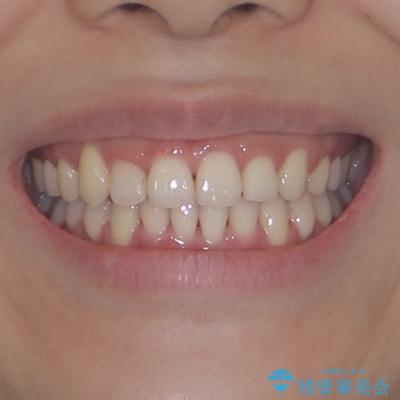

- 上下前歯のデコボコを気にして来院された患者様です。

上顎歯列が下顎の歯列に対して狭小であり、一部下顎の奥歯が上顎よりも外側に位置している状態でした。

上顎の急速拡大装置を使用して上顎骨を側方に拡大することで上顎歯列を拡大し、下顎歯列も拡大できるようにすることで、歯列を整えることとしました。